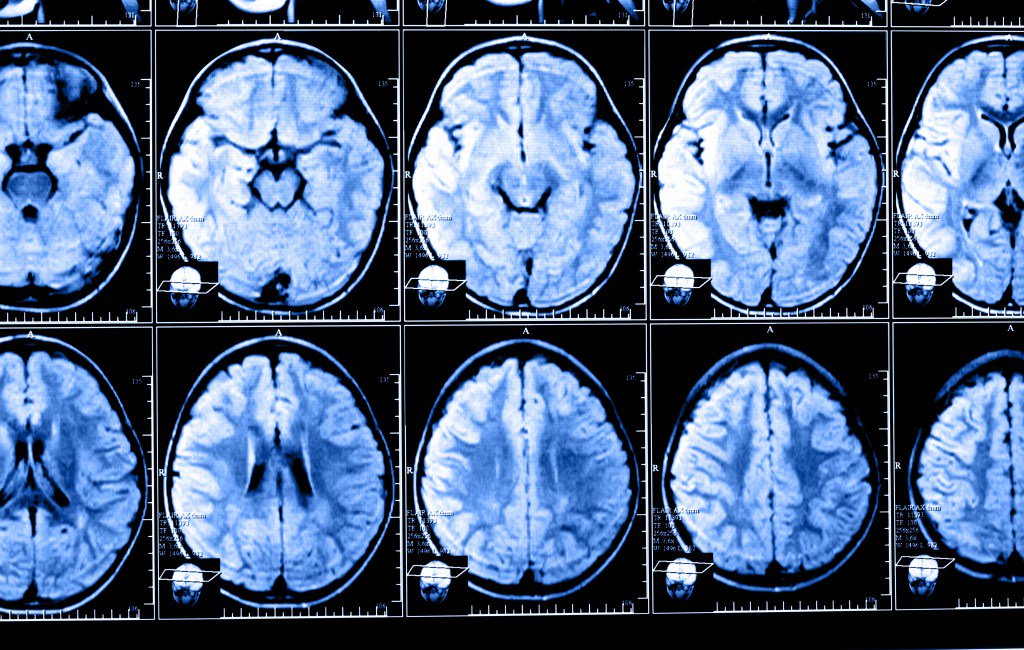

Using functional magnetic resonance imaging (fMRI), the researchers performed brain scans on 37 FM patients and 35 healthy controls. All subjects were exposed to painful pressure and non-painful visual, auditory, and tactile cues during the scans.

Computerized machine-learning techniques allowed the researchers to identify a brain-based FM signature. Specifically, when exposed to the same painful stimuli as people in the healthy control group, FM patients showed greater neurologic pain signature responses. The method relies on a computer algorithm developed by CU Bolder researchers to recognize a complex pattern of neuronal activation in the brains of subjects exposed to pain.